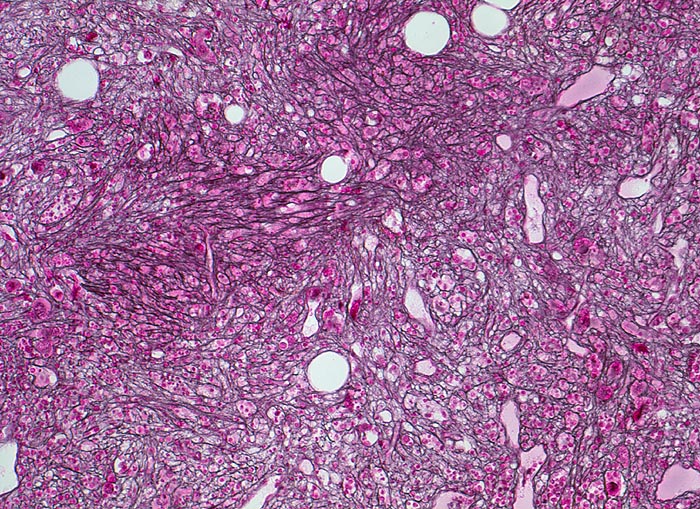

- Osteosklerose: verplumpte und breite Knochenbälkchen.

- Kollagenfibrose.

- Dilatierte Sinusoide mit intrasinusoidaler Blutbildung.

- Vermehrung von atypischen, in Gruppen liegenden Megakaryozyten mit abnorm lobulierten Kernen.

- Nacktkernige (zytoplasmaarme) und vergrösserte Megakaryozyten.

- Hyperplastische ausreifende Myelopoese.

- Hypoplastische Erythropoese.

- Retikulinfaserfibrose des Marks vorhanden aber in der HE Färbung schwierig quantifizierbar.